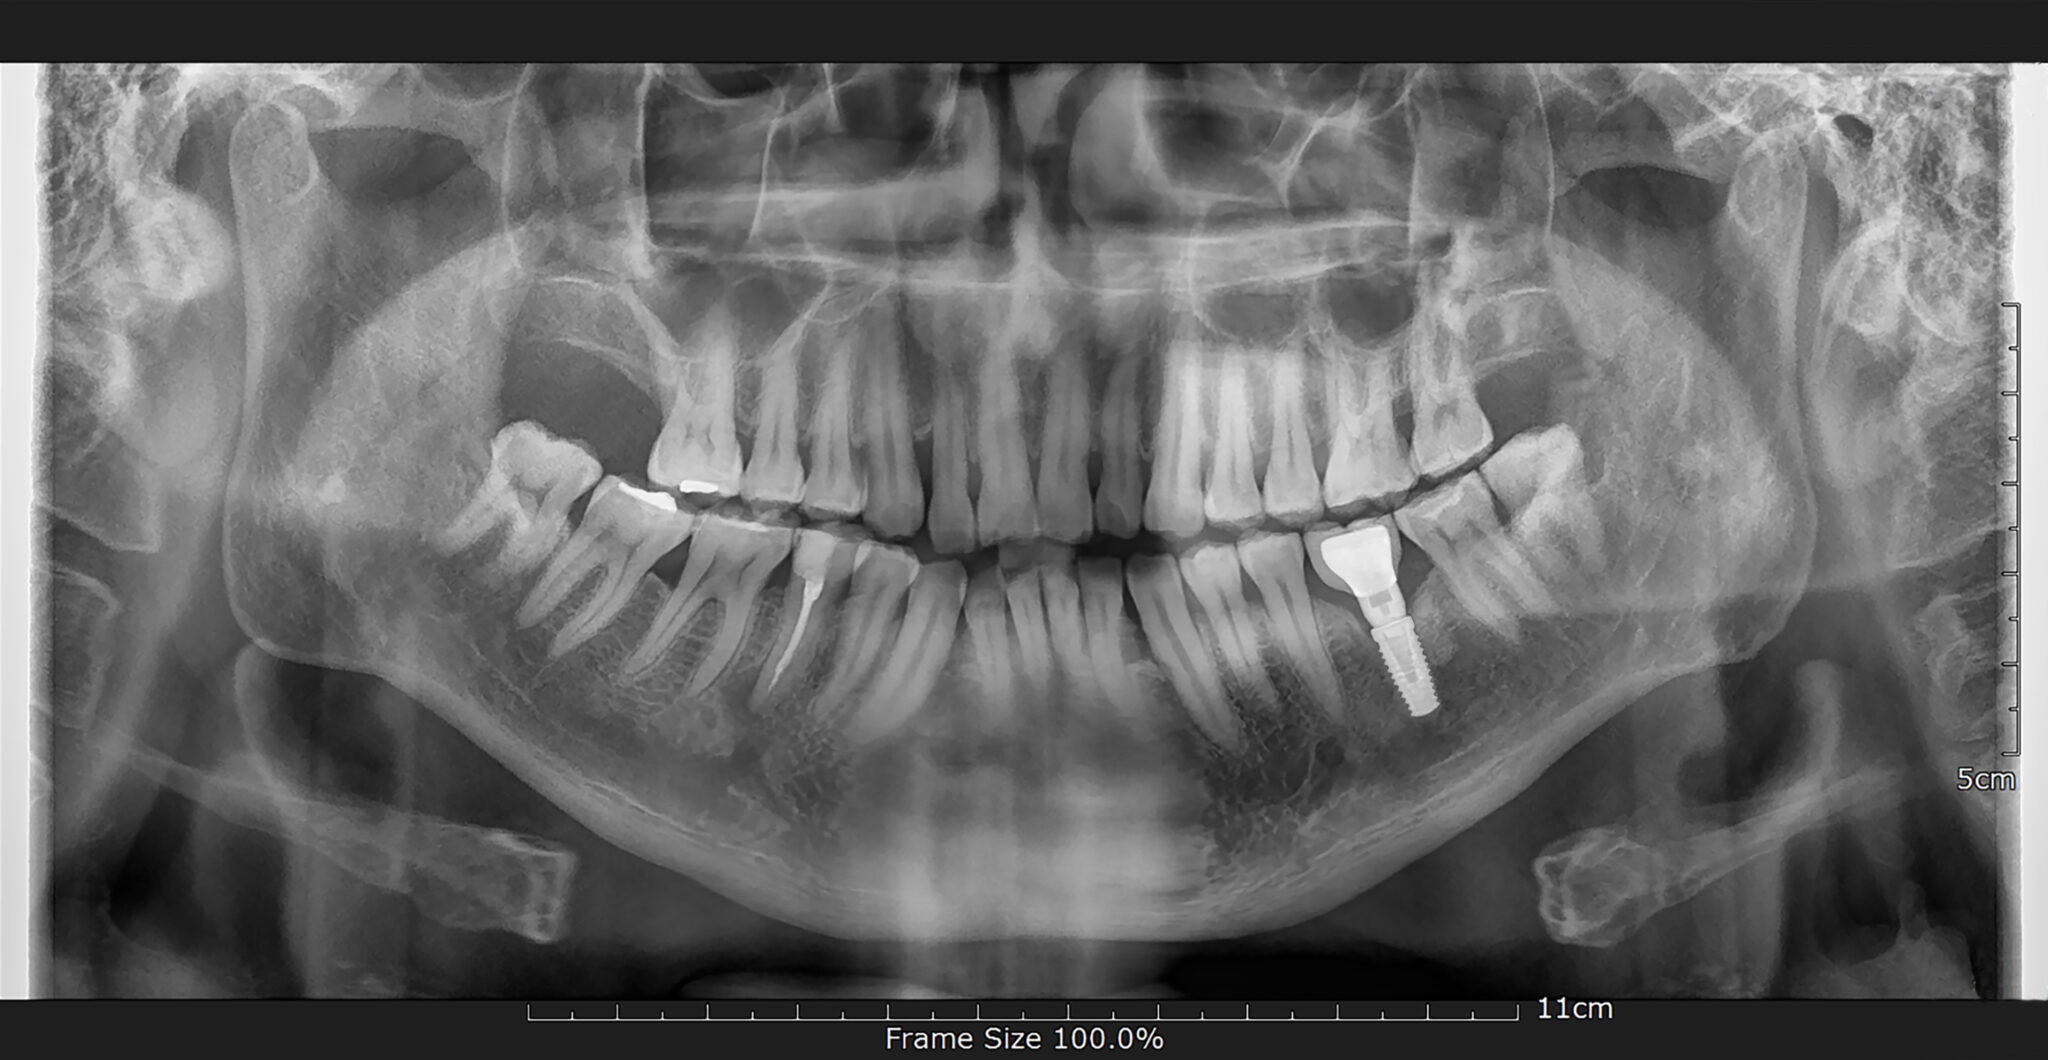

Prognosis of Implants in Previously Failed Surgical Sites

Introduction Implant therapy has been shown to be predictable, effective and reliable for the replacement of missing teeth in edentulous and partially edentulous patients. Clinical evidence has demonstrated long-term (>10 years) survival rates up to 95% (Moraschini et al., 2015). Despite the high success and survival rates of dental implants, failures can and do occur. … Read more